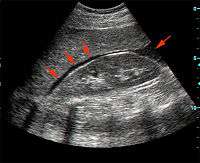

Ultrasonographic view of the abdomen demonstrating fluid within Morison's pouch.

Morison's pouch with fluid present (at red arrows).